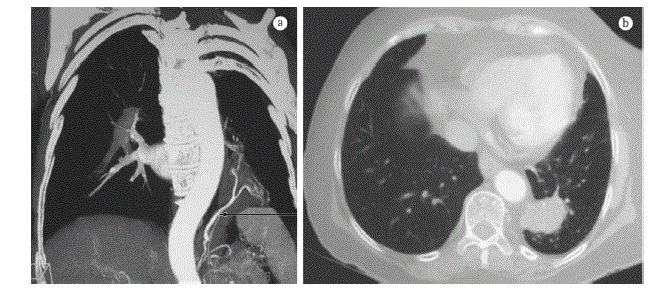

Paciente de 10 anos de idade vem evoluindo com episódios de infecções de repetição no último ano, necessitando de internamento hospitalar no último episódio. Recebeu alta hospitalar e iniciou acompanhamento com pneumopediatra que solicitou tomografia de tórax para investigação.

Diante da imagem da tomografia, qual a principal hipótese diagnóstica e o tratamento a ser instituído?